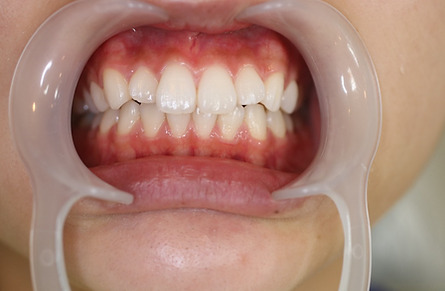

2ホワイトニング【治療例1】

治療前

治療後